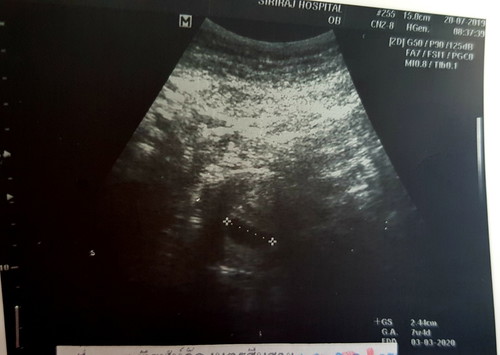

U/S ผ่านหน้าท้อง 6 Weeks ไม่เห็นตัวเด็ก

ปกติไหมคะ เห็นถุงตั้งครรภ์ 2.4 cm. อายุครรภ์ในเครื่องบอกว่า 7 w. แต่จริงๆคือ 6 w ไม่เห็นอะไรเลย นอกจากถุงตั้งครรภ์ หมอนัดอีกทีอีกสองสัปดาห์ค่ะ

เป็นปกติจ้า ซาวด์ทางหน้าท้องจะเห็นได้ยากค่ะ อายุครรภ์ยังน้อย ตัวอ่อนยังเล็กมาก ถ้าอยากเห็นไวๆ ต้องให้คุณหมอซาวด์ทางช่องคลอดให้จ้า

ใจเย็นๆน้าคุณแม่ น้องยังเล็กมาก ช่วงนี้บำรุงตัวเองไปเลยนะคะ และไปตามหมอนัดเลยจ้า เดี๋ยวครั้งหน้าก็เจอกัน